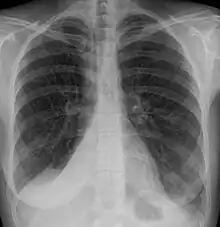

| Atelectasis of a person's right lung | |

Atelectasis is the partial collapse or closure of a lung resulting in reduced or absence in gas exchange. It is usually unilateral, affecting part or all of one lung.[2] It is a condition where the alveoli are deflated down to little or no volume, as distinct from pulmonary consolidation, in which they are filled with liquid. It is often referred to informally as a collapsed lung, although more accurately it usually involves only a partial collapse, and that ambiguous term is also informally used for a fully collapsed lung caused by a pneumothorax.[1]

Clinically significant atelectasis is generally visible on chest X-ray; findings can include lung opacification and/or loss of lung volume. Post-surgical atelectasis will be bibasal in pattern. Chest CT or bronchoscopy may be necessary if the cause of atelectasis is not clinically apparent. Direct signs of atelectasis include displacement of interlobar fissures and mobile structures within the thorax, overinflation of the unaffected ipsilateral lobe or contralateral lung, and opacification of the collapsed lobe. In addition to clinically significant findings on chest X-rays, patients may present with indirect signs and symptoms such as elevation of the diaphragm, shifting of the trachea, heart and mediastinum; displacement of the hilus and shifting granulomas.[11]